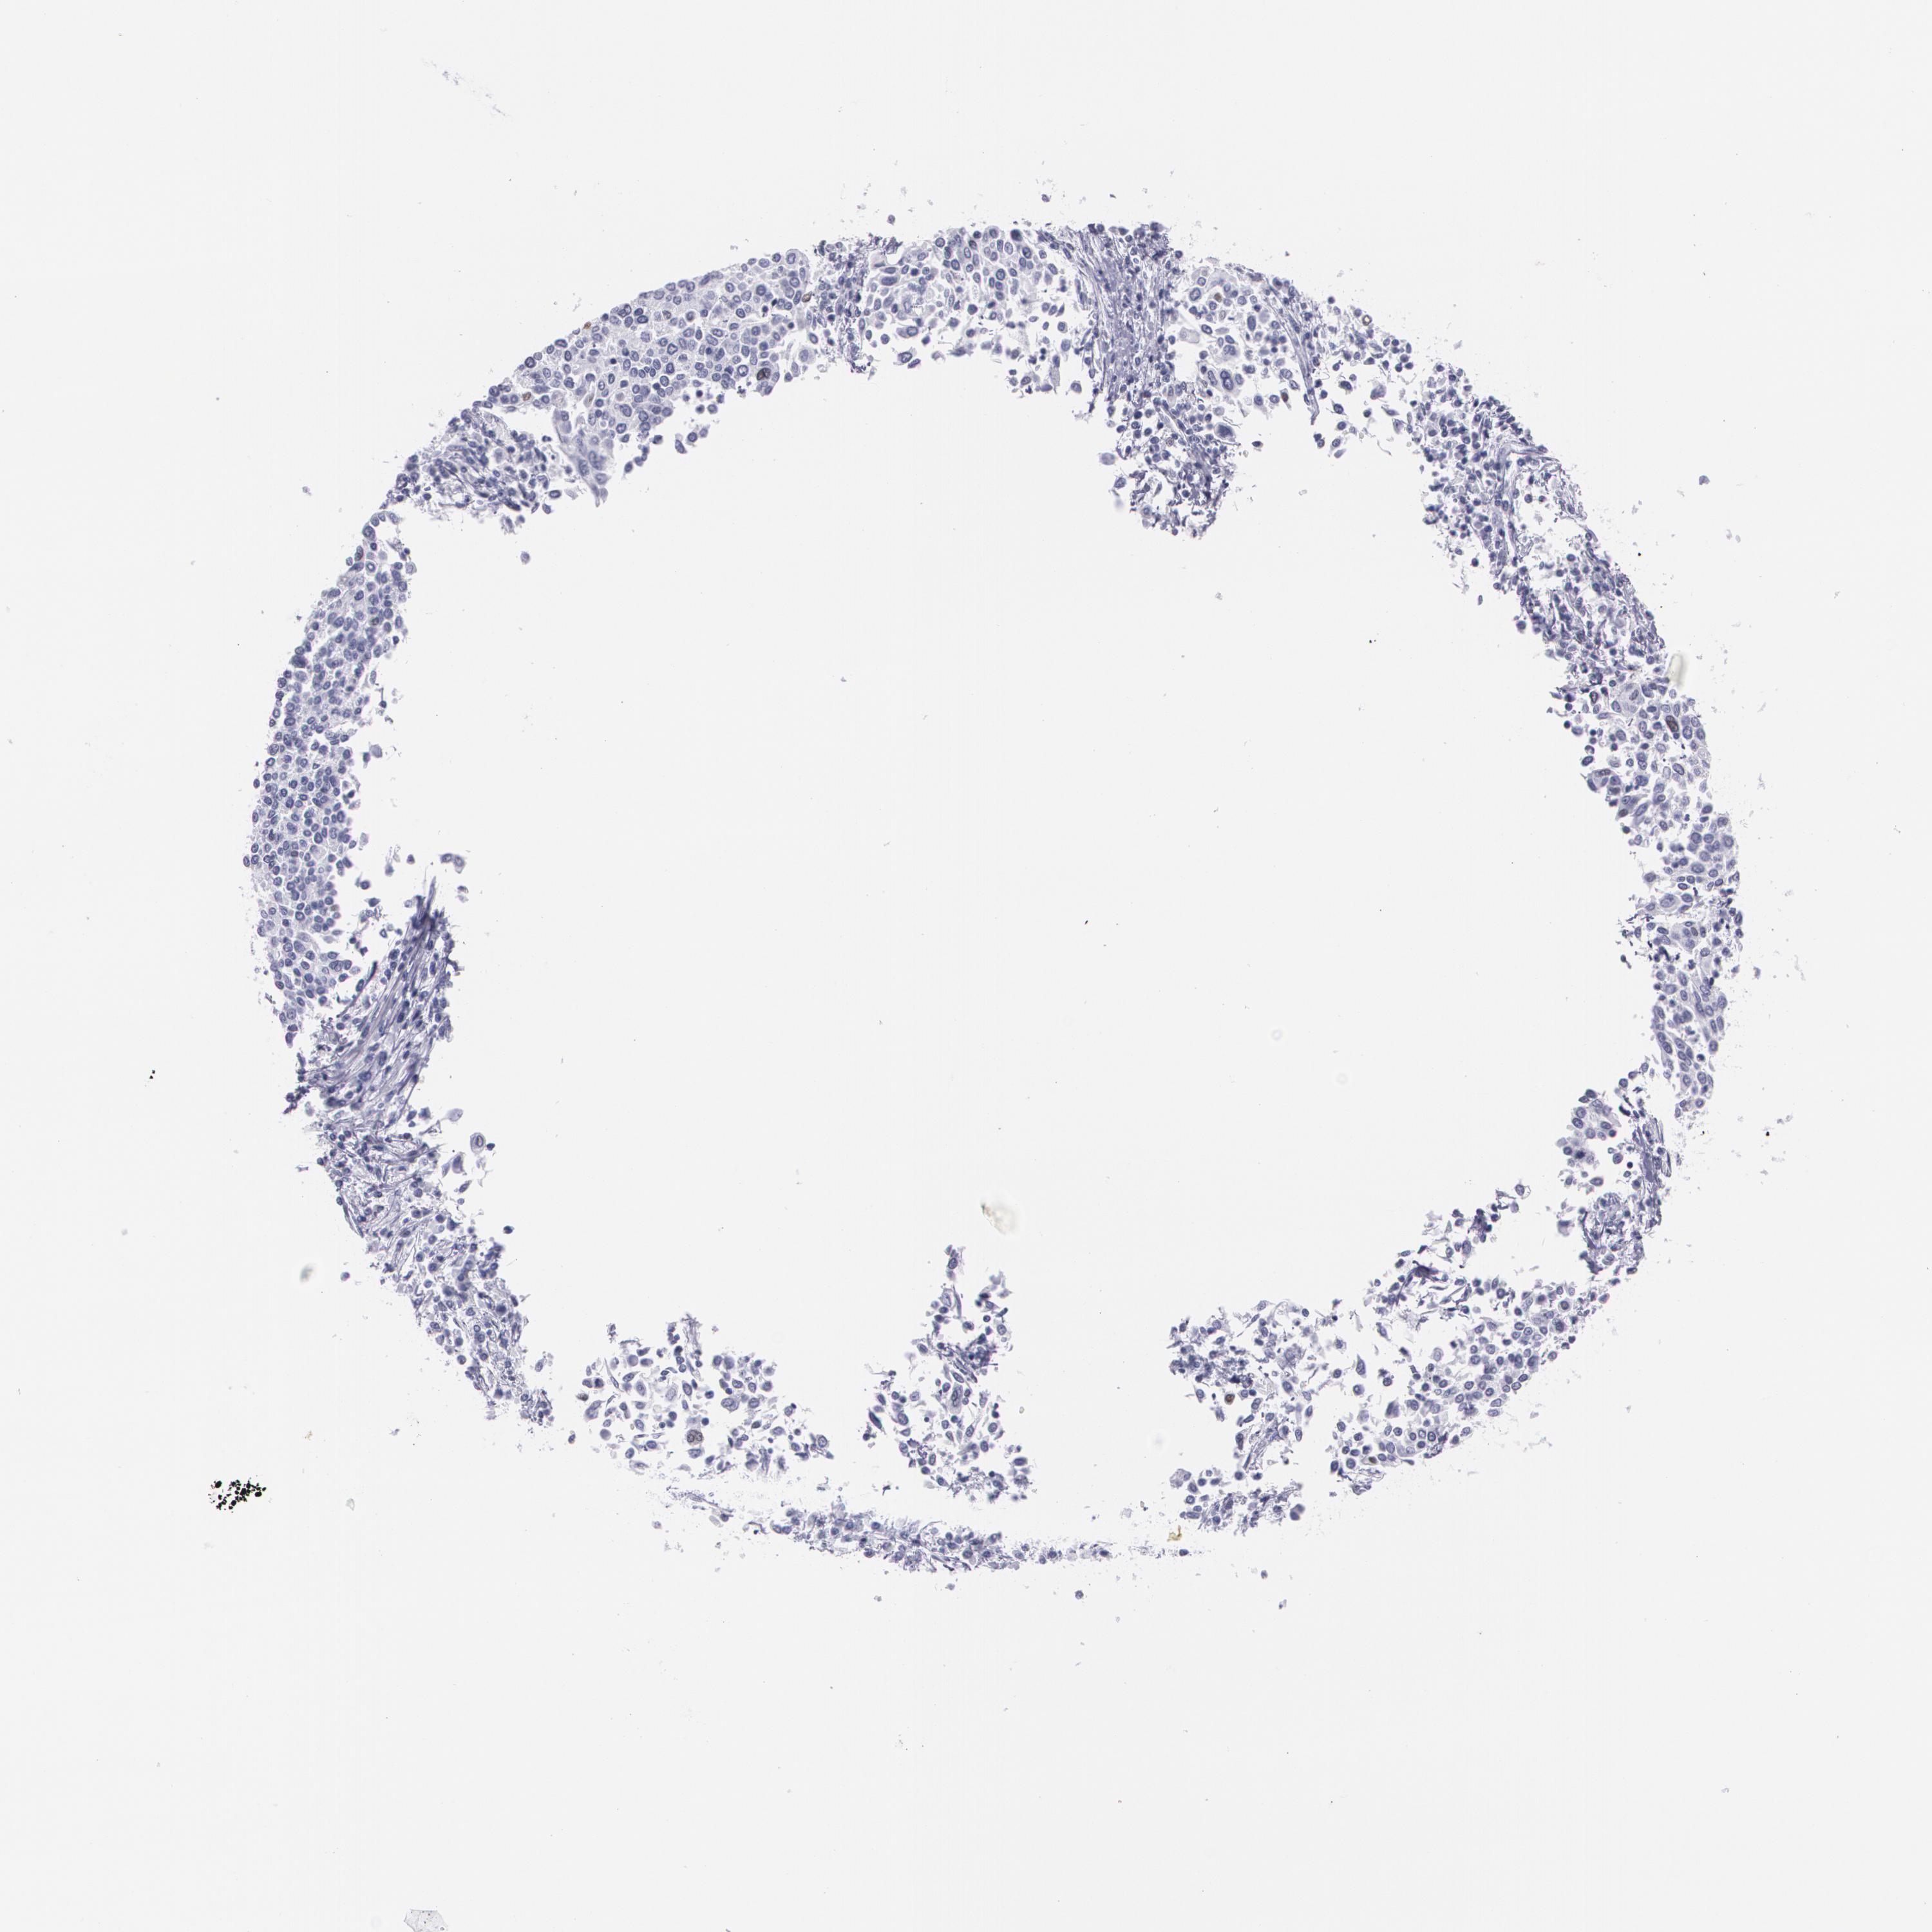

CERVICAL CANCER - Protein expressioni

A mouse-over function shows sample information and annotation data. Click on an image to view it in a full screen mode. Samples can be filtered based on level of antibody staining by selecting one or several of the following categories: high, medium, low and not detected. The assay and annotation is described here.

Note that samples used for immunohistochemistry by the Human Protein Atlas do not correspond to samples in the TCGA dataset.

Antibody stainingi

Antibody staining in the annotated cell types in the current human tissue is reported as not detected, low, medium, or high, based on conventional immunohistochemistry profiling in selected tissues. This score is based on the combination of the staining intensity and fraction of stained cells.

Each image is clickable and will lead to virtual microscopy that enables deeper exploration of all samples and also displays staining intensity scores, fraction scores and subcellular localization as well as patient and tissue information for each sample.

Antibody CAB002973

Antibody CAB039238

Antibody CAB039239

Antibody CAB072876

Squamous cell carcinoma, NOS